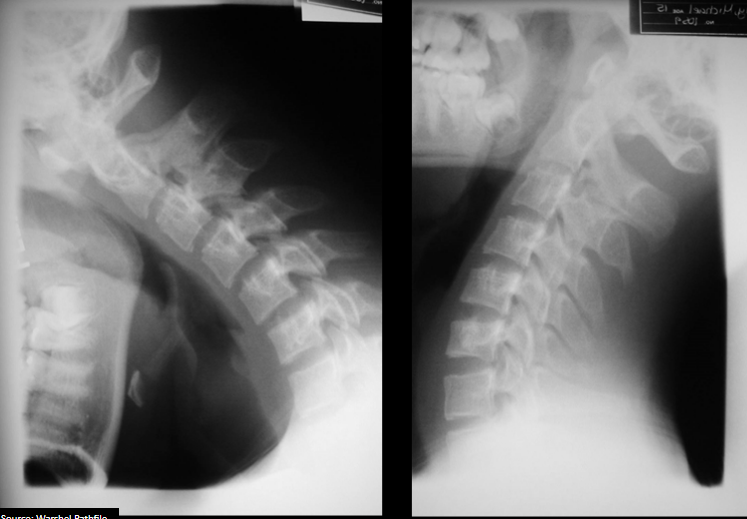

21

Which cervical line has the most pertinent abnormality?

A

Anterior body line displays slight anterolisthesis

unilateral facet dislocation

22

What is the diagnosis and mechanism of injury?

Is this stable or unstable?

Unilateral facet dislocation due to flexion with rotation (towards side of dislocation)

Stable until reduced

treat as unstable